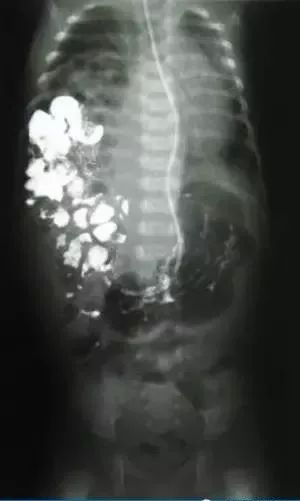

全血细胞计数显示13×10³/µL ,白细胞计数:13×10^9/L,中性粒细胞45%、淋巴细胞42%、嗜酸性粒细胞3%。暂无血气分析。X线如下图,拍片过程中未见右侧膈肌移动。

根据临床表现,辅助检查如X线检查可见患侧膈肌升高,可升到第三、四前肋间隙高度,膈下紧贴胃泡,膈肌厚度明显变薄,胸透可见患侧膈肌活动受限或消失,有时可见矛盾运动,尤其是后天性膈膨出者更为明显。